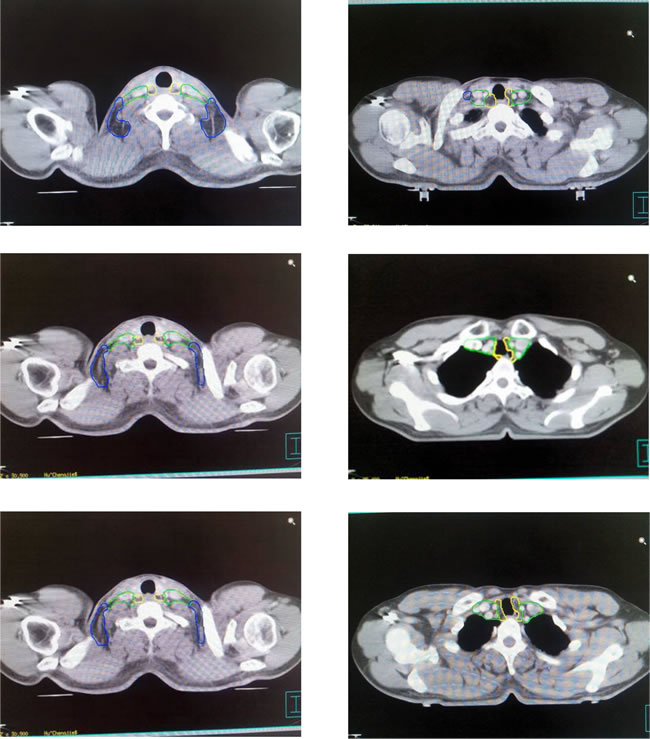

According to the reported method [13, 14], with muscles, bones and blood vessels as the main marker points, the lymph nodes in lower neck of esophageal cancer were zoned as long as they can be delineated based on CT-images in principle. In addition, the zones were divided into three zones, cervical tracheoesophageal groove (CTG zone), medial supraclavicular zone (MSC zone) and lateral supraclavicular zone (LSC zone). Moreover, six bounds for each zone were defined in Table 2. And the schematic diagrams of zoning at different CT bedding planes were indicated in Figure 1.

Figure 1: Schematic diagrams of zoning at different bedding planes of CT-imaging in lymphatic drainage area. Note: Zones encircled with yellow line are CTG zones, those with green line are MSC zones and those with blue line are LSC zones.